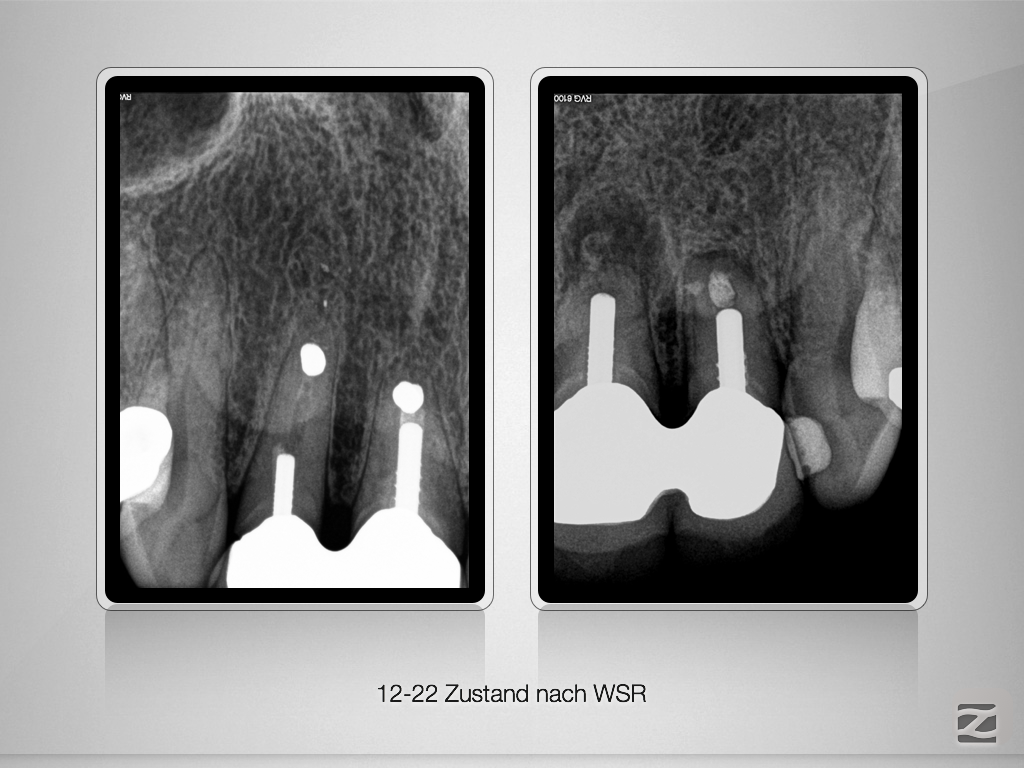

Viermal das Gleiche und doch nicht Dasselbe